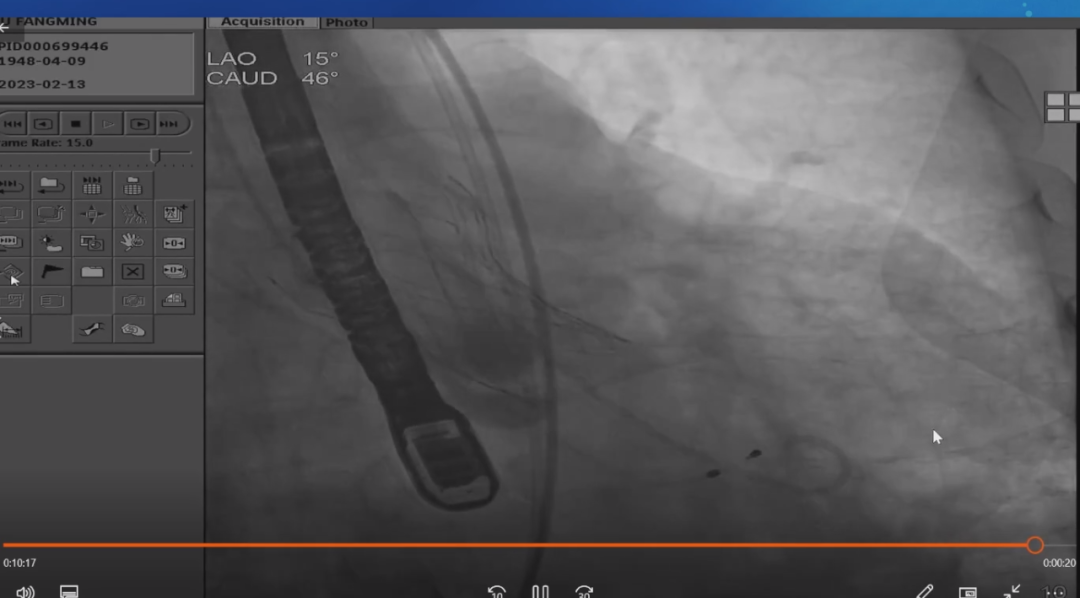

华正东教授:手术采用经股动脉路径,无球囊预扩张,使用沛嘉公司TaurusElite 31#可回收瓣膜,初始“零位”释放发生瓣架下滑,部分回收后进行第二次释放。第二次定位高于“零位”1~2 mm,充分固定导丝,输送鞘尽量靠近大弯侧。140bpm快速起搏,瓣架底边贴靠无冠窦底后快速释放至“可回收”,停临时起搏,经食道超声评估瓣膜定位良好,无明显瓣周漏,后完全释放瓣膜。主动脉根部造影评估,冠脉显影良好,轻微瓣周漏,结束手术。